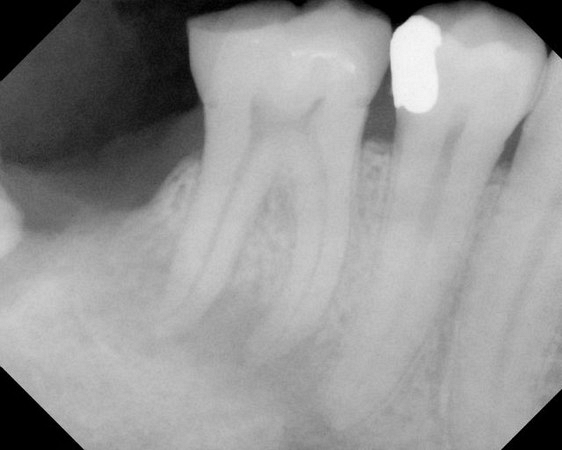

Here are examples of digital dental radiography